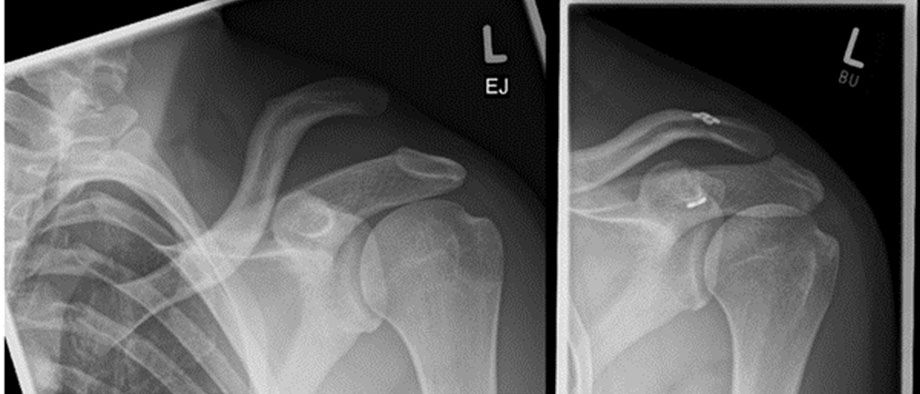

Eine Schultereckgelenkssprengung entsteht meist durch einen Sturz auf die Schulter. Dabei werden die stabilisierenden Bänder des AC‑Gelenks unterschiedlich stark verletzt. Leichtere Verletzungen behandeln wir konservativ mit Schmerzmitteln, kurzer Ruhigstellung und anschließender Physiotherapie zur Stabilisierung. Bei ausgeprägten Bandverletzungen ist eine Operation sinnvoll. Wir rekonstruieren die Bänder minimalinvasiv mit dem modernen Dogbone‑Button‑Verfahren, um die ursprüngliche Stabilität wiederherzustellen. Bei hoher beruflicher oder sportlicher Belastung wird häufiger operiert, um eine dauerhafte Instabilität zu vermeiden. Chronische Verletzungen können einen Sehnenersatz erfordern. Ziel ist eine individuell angepasste Therapie für eine stabile, belastbare und schmerzfreie Schulter.

Linkes Bild: Schlüsselbeinhochstand, sogenanntes Klaviertastenphänomen. Die stabilisierenden Bänder sind gerissen. Rechtes Bild: nach arthroskopischen Einbringen von 2 „Dogbone buttons“ sind die anatomischen Verhältnisse wieder hergestellt. Der Hochstand des Schlüsselbeins ist aufgehoben. Bis die körpereigenen Bänder wieder verheilt sind schützt das flaschenzugähnliche Konstrukt zwischen den zwei Metallplättchen die körpereigenen Bänder vor Belastung und übernimmt deren Funktion.